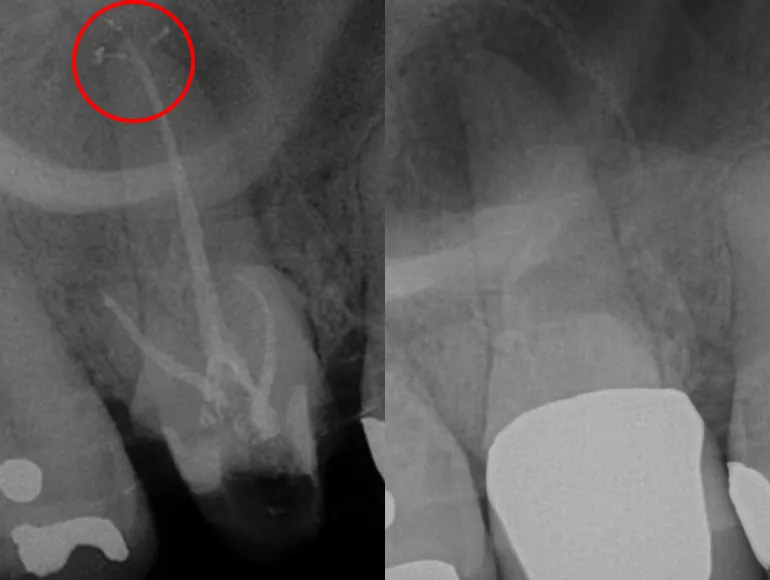

Accessory Canals

Rootcanal therapy through dental prosthesis

Case by Dr. Taha Azimaie: Retreatment of rootcanal through dental prosthesis can save patient money and dental visits. This tooth endodontically treated and was part of a dental bridge. The tooth also contained a long pin (AKA post) that is cemented deep in the canal, removal of a post is a challenging procedure and can lead to tooth fracture. In this case, an access hole made through the bridge and post removed. Root canal therapy retreated and the access hope filled with dental filling material. Now this dental bridge can last longer and may not require replacement.